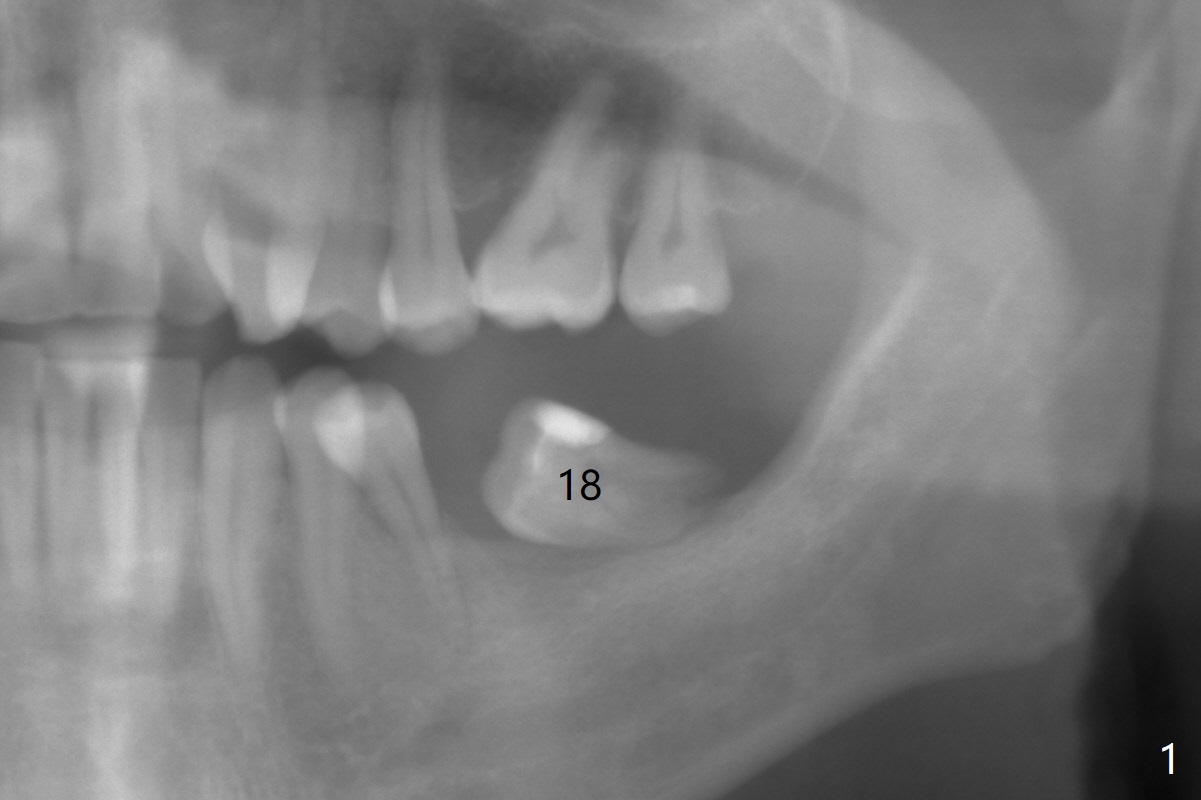

A 43-year-old man has poor dentition on the left: 1st molar missing, 2nd molar mesial inclination (Fig.1) and 2nd bicuspid lingual tilt (Fig.2). The latter is nonfunctional (Fig.3 (linguoposterior view). Two molar implants will be placed in a position so that their crowns will be in cross bite (Fig.4,5), the same occlusal scheme as the teeth #21 and 22. When these implants osteointegrate, the provisional crowns (Fig.6 P) will be supraocclusal so that there is clearance (*) for #20 to upright orthodontically (Fig.7-9). Moreover, these implants will be used anchorage as well as #21 and 22. Panoramic X-ray (Fig.1) and CBCT (Fig.10-12) show limited bone height at the sites of #18 and 19. It appears that 5x8 and 5.9x6 mm implants are appropriate with ridge reduction at #19.